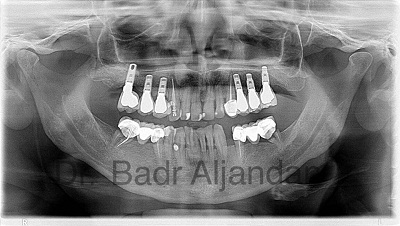

The implants themselves are tiny titanium posts, which are inserted into the jawbone where teeth are missing. These metal anchors act as tooth root substitutes. They are surgically placed into the jawbone. The bone bonds with the titanium, creating a strong foundation for artificial teeth. Small posts are then attached to the implant, which protrude through the gums. These posts provide stable anchors for artificial replacement teeth.

For most patients, the placement of dental implants involves two surgical procedures. First, implants are placed within your jawbone. For the first three to six months following surgery, the implants are beneath the surface of the gums gradually bonding with the jawbone. You should be able to wear temporary dentures and eat a soft diet during this time. At the same time, your dentist is forming new replacement teeth.

After the implant has bonded to the jawbone, the second phase begins. Dr. Al-jandan will uncover the implants and attach small posts that protrude through the gums and will act as anchors for the artificial teeth. When the artificial teeth are placed, these posts will not be seen. The entire procedure usually takes six to eight months. Most patients experience minimal disruption in their daily life.

Dental Implant placement is a team effort between an oral and maxillofacial surgeon and a restorative dentist. While Dr. Al-jandan performs the actual implant surgery, initial tooth extractions, and bone grafting if necessary, the restorative dentist (your dentist) fits and makes the permanent prosthesis. Your dentist will also make any temporary prosthesis needed during the implant process.

A single prosthesis (crown) is used to replace one missing tooth – each prosthetic tooth attaches to its own implant. A partial prosthesis (fixed bridge) can replace two or more teeth and may require only two or three implants. A complete dental prosthesis (fixed bridge) replaces all the teeth in your upper or lower jaw. The number of implants varies depending upon which type of complete prosthesis (removable or fixed) is recommended. A removable prosthesis (over denture) attaches to a bar or ball in socket attachments, whereas a fixed prosthesis is permanent and removable only by the dentist.